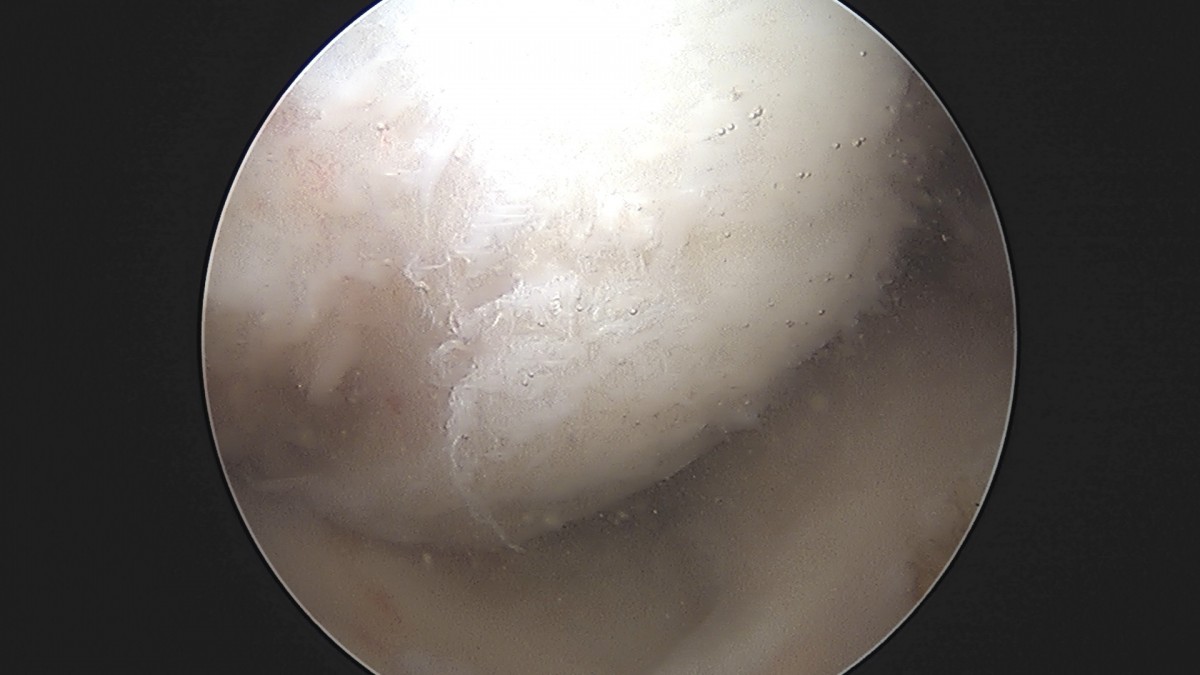

정지영원장님 무릎 반월상 연골판 절제술 이영O 환자

dae765e4d9ac96aee867c9d6292d8784_1758009377_7501.jpg